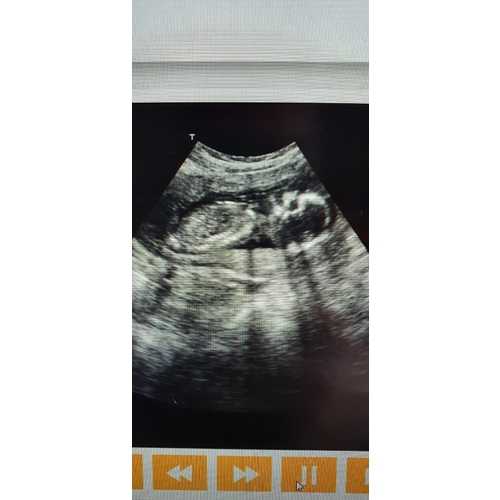

Dat kan ik zeker even doen mijn echo apparatuur begon vandaag te storen met slecht beeld babywatcher gaat morgen van afstand probleem op lossen en krijg een extra dag ik zal morgen dan even een echo foto hier uploaden

Zelfde probleem hier kreeg 3 dagen extra maar wat een kwaliteit -.-“ krijg gelukkig me geld terug vind het dikke bagger

Ik vond het best wel duidelijk, vooral als hij veel beweegt! Maar die kan ik niet uploaden, wel heel leuk om terug te kijken

Ik heb ook meer problemen gehad, dan dat hij daadwerkelijk goed werkte. Meerdere dagen was er geen baby van te maken op het beeld 🤣 computer liep op om de haverklap vast terwijl de echo tijd doorliep